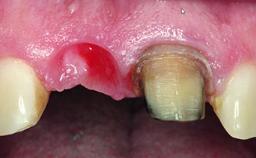

A 30-year-old patient presented at our clinic with a chief complaint of pain in her endodontically treated right maxillary central incisor (tooth 11) with a post-and-core and a fixed single crown. She had a very high lip line, a medium to thin soft-tissue phenotype, and a medium scalloped gingival contour. She also had high esthetic expectations because of her young age and beautiful smile. However, her expectations were realistic and she understood the risks of the treatment. At the initial clinical examination there was a slight mobility of tooth 11; no fistula was observed. The patient also had a single crown on the adjacent tooth 21. Both restorations were old and esthetically deficient. A digital periapical radiograph showed a very small periapical radiolucency, a thick intraradicular post, and no separation between root fragments.

Bone Augmentation Staged

Augmentation Materials Xenogenous|Membrane

Soft Tissue Grafting Simultaneous